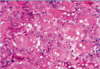

A: Describe Histology (5)

B: Dz

C: Location

D: Demographic

A:

- [Hyperkeratosis (light purple in top L)]

- Epidermal Acanthosis made of uniform small keratinocytes

- Horn Cyst

- [Flat Base String Sign] = no infiltration into dermis

- [Papillated Undulated Epithelium] (Papillomatosis)

B: Seborrheic Keratosis

C: Anywhere on Skin [except palms/soles]

D: Pt > 30 y/o